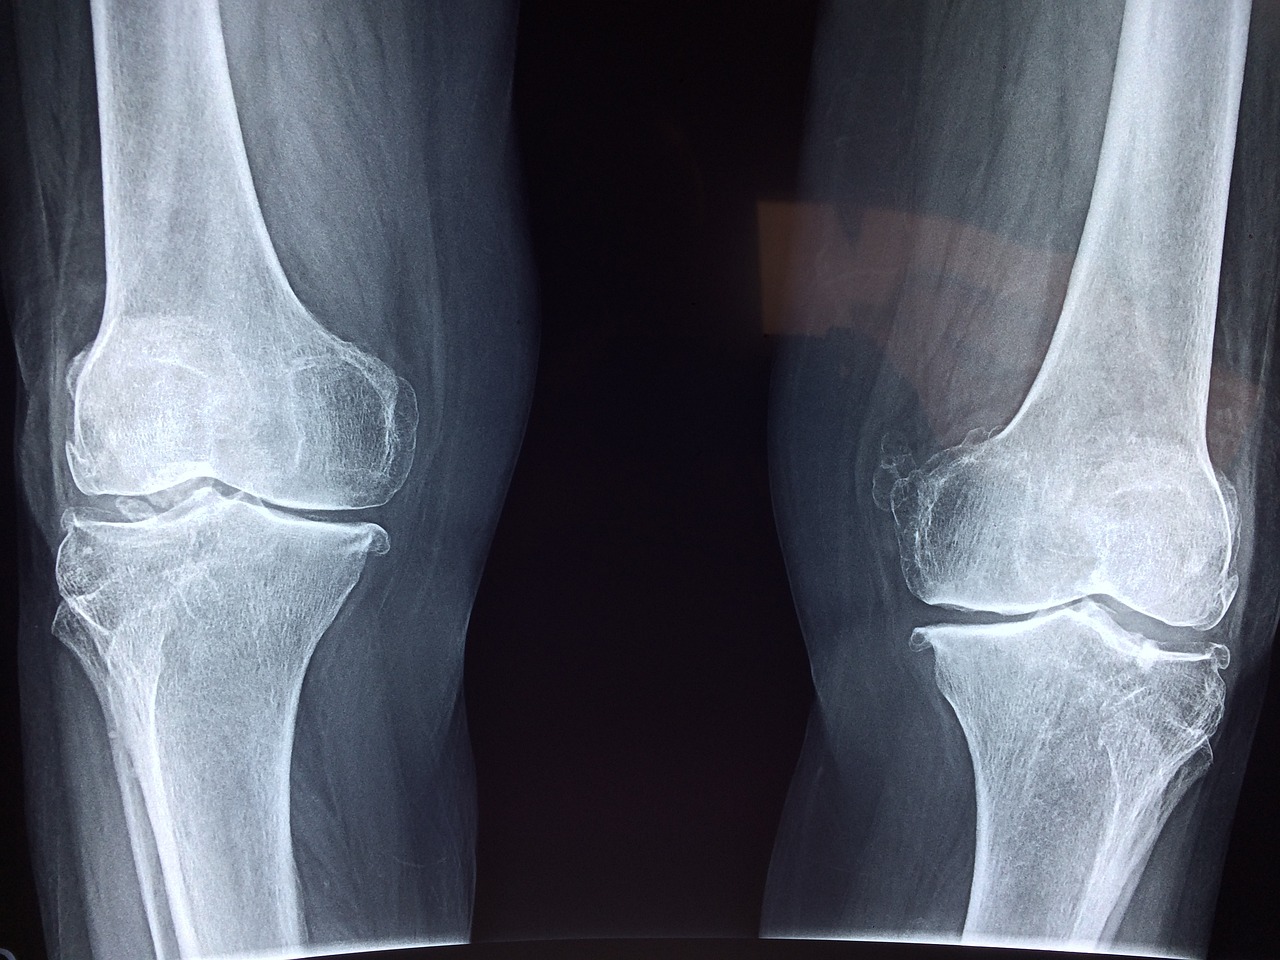

관절을 보호하고 있는 연골의 손상이나 퇴행성 변화로 인해 관절을 이루는 뼈와 인대 등에 손상이 생겨 염증과 통증이 발생하는 질환으로 관절 질환 중에서 가장 많이 발생하는 질환입니다.

6) 변형

시간이 지남에 따라 관절 모양이 변형될 수 있습니다.

손가락 관절염의 경우 손가락이 구부러지거나 굽어질 수 있습니다.

이러한 증상들은 점진적으로 나타나며, 초기에는 가벼운 불편함으로 시작되지만 점차 심해질 수 있습니다.